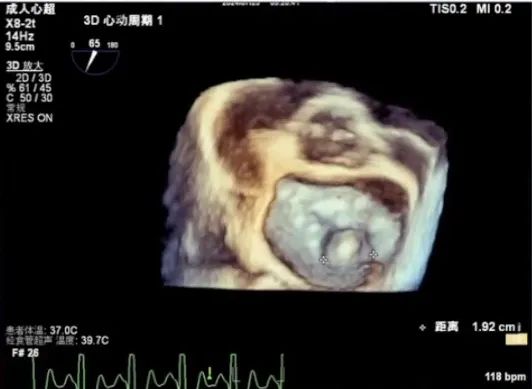

经食道超声检查

经食道检查结果显示,1区瓣叶结构良好,主要脱垂集中于P2区,3区未见明显受累。

进一步评估患者病变情况,前叶长度2.74mm,后叶长度1.93mm;房间隔前后径4.0cm,房间隔长径6.9cm,瓣口面积6.27cm²,平均跨瓣压差5mmHg。